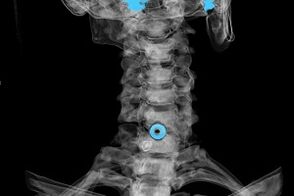

Rozpoznanie ustala się na podstawie charakterystycznych objawów, a także na podstawie:

- Promienie rentgenowskie. Metoda jest nieskuteczna, szczególnie w ostatnich stadiach rozwoju osteochondrozy.

- MRI (rezonans magnetyczny) kręgosłupa szyjnego. Metoda pozwalająca zobaczyć struktury kostne, przepukliny krążków międzykręgowych, ich wielkość i kierunek rozwoju.

- Tomografia komputerowa. Mniej skuteczne rozwiązanie niż MRI, ponieważ trudno jest określić obecność i wielkość przepuklin.